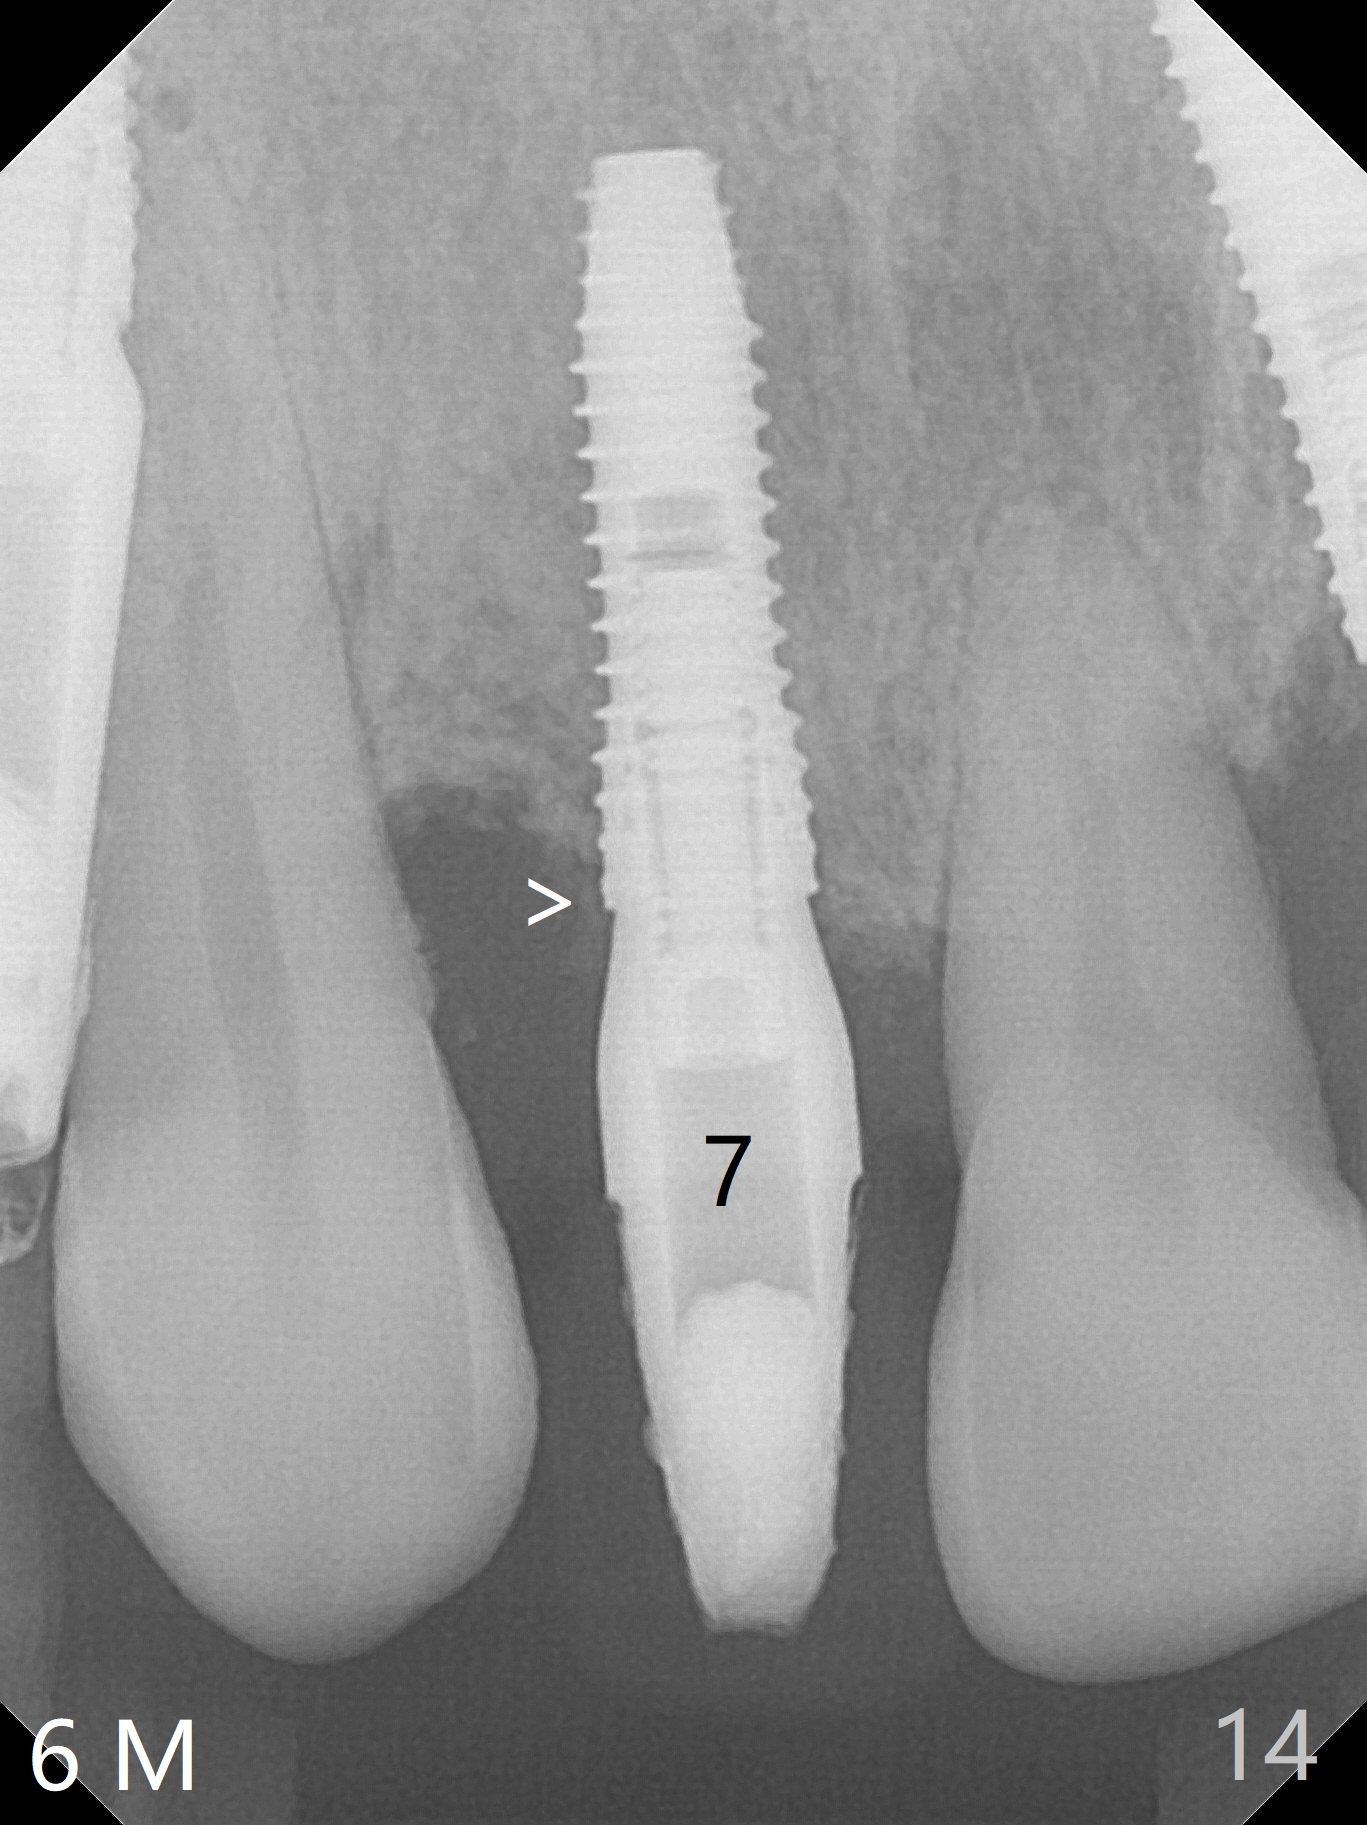

When a 3.8x13 mm implant is placed at #7 (50 Ncm), an angled abutment is used (Fig.4, 4.5x15°(A)5 mm). The distal threads appear to have been covered by the regenerated bone 6 months postop (Fig.14 >).